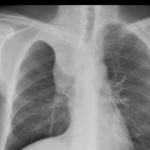

Sarcoid

Album: Sarcoid

Date: 04/20/2004

Size: 63 items

Views: 38606